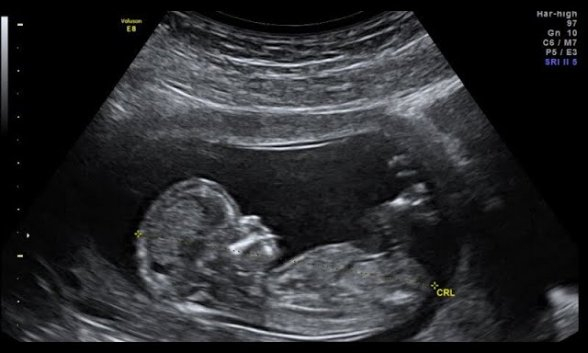

Detrás de estos proyectos se busca dar un nuevo paso y reconocer legalmente la personalidad del embrión. Eso es, por supuesto, algo que el movimiento provida siempre había deseado, pero realmente no se había podido lograr de la misma manera que ahora sin el caso Roe v. Wade”, dijo Mary Ziegler, profesora de derecho en la Universidad de California, Davis. Los republicanos de los proyectos de ley han argumentado que los fetos son “tan humanos como nosotros” y deberían ser tratados legalmente como tales. Algo que ya defendió Benedicto XVI y que lo resume todo: Dios ama al embrión.